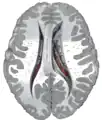

This is a transverse view of the caudate nucleus from a structural MR image.

Transverse view of the caudate nucleus from a structural MR image